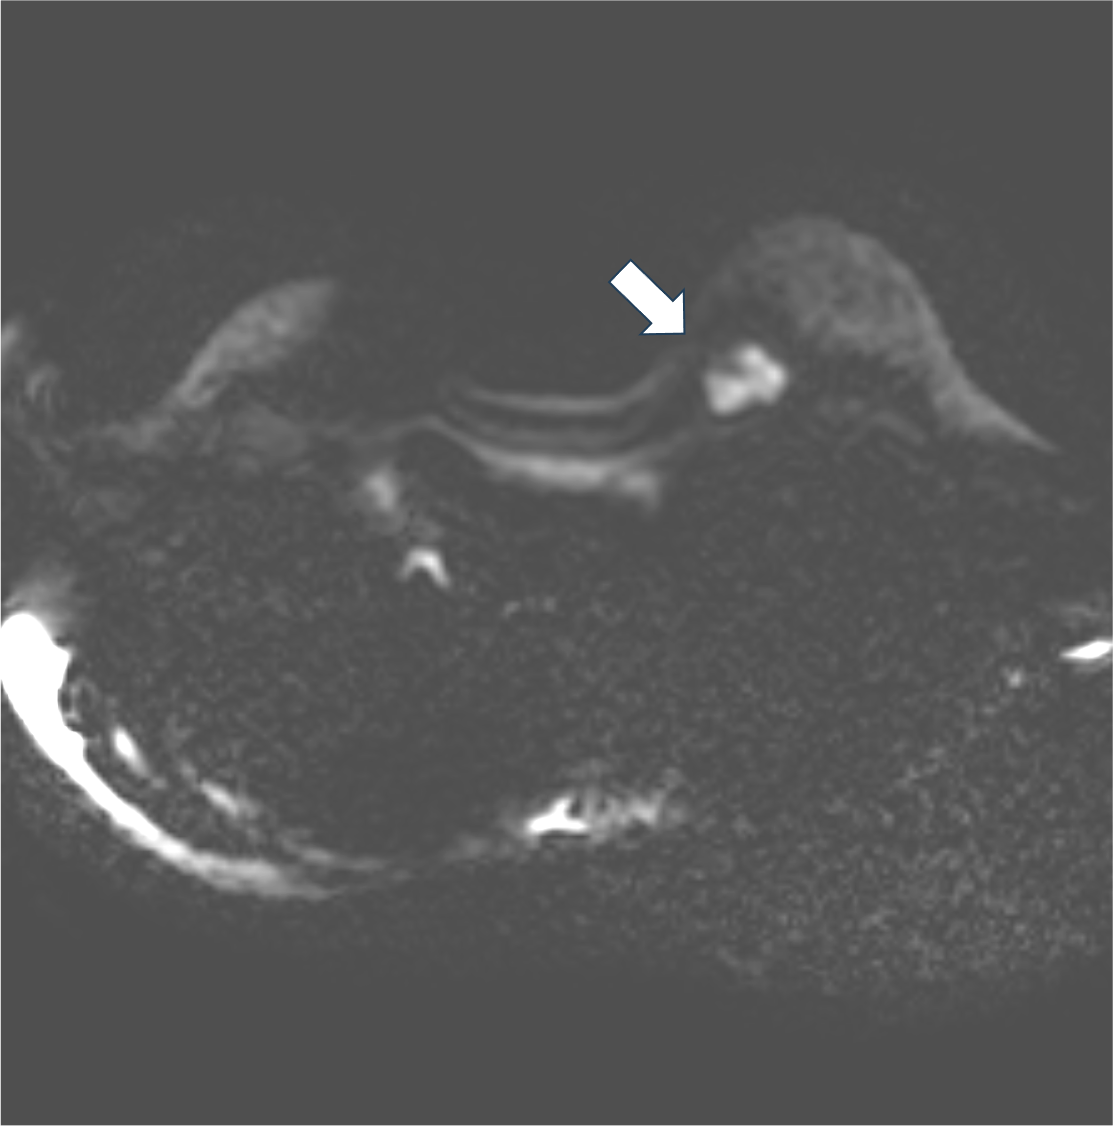

3. 拡散強調画像 b=1000(s/mm2)(造影前)

拡散強調像では明瞭な高信号を示す。細胞密度の高い腫瘍が示唆される。